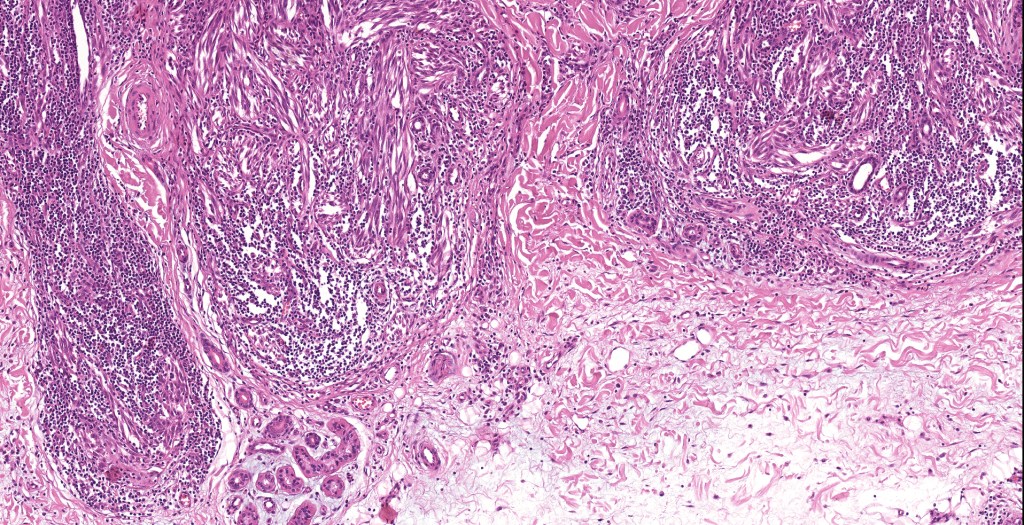

•Sharply circumscribed (begins and ends with a nest), symmetrical dome-shaped lesion. Symmetry is both horizontal and vertical (see image below)

•Wedge-shaped with the base uppermost or sometimes plaque-shaped silhouette

•Matures with depth-often best recognized at scanning/low power magnification & readily confirmed with S100 or MART1

•Maturation implies nest size and cell size diminishing with depth, at the base, the infiltrate may have a single cell infiltrating pattern

•Hyperkeratosis & acanthosis, sometimes very marked

•Superficial vascular ectasia very frequently present

•Lymphocytic infiltration at the base of the lesion